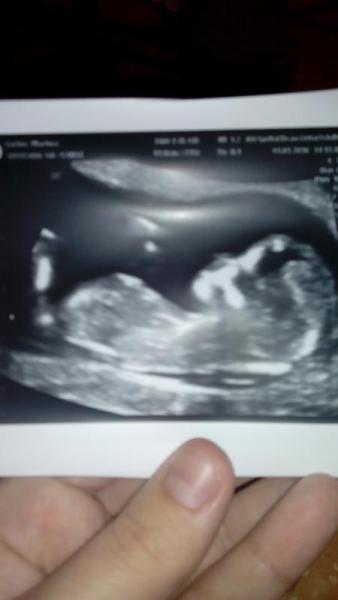

Bild zu

Das bild passt auch nicht wirklich zur 9 ssw.. eher zur 14... Dann stimmt das in etwa mit 8 cm

Sorry, aber das Bild sieht exakt nach 9 SSW aus. Kannst du sonst auch googlen.

Also er wird wohl 8 mm gemeint haben, das Bild passt auf die 9ssw. Hänge mal mein Bild von der 9ssw an.